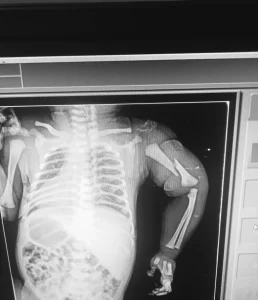

आरोप है कि डॉक्टर ने नवजात को पिता से छीनकर जमीन पर फेंक दिया, जिससे बच्चे को गंभीर चोट पहुंची और उसका हाथ टूट गया।